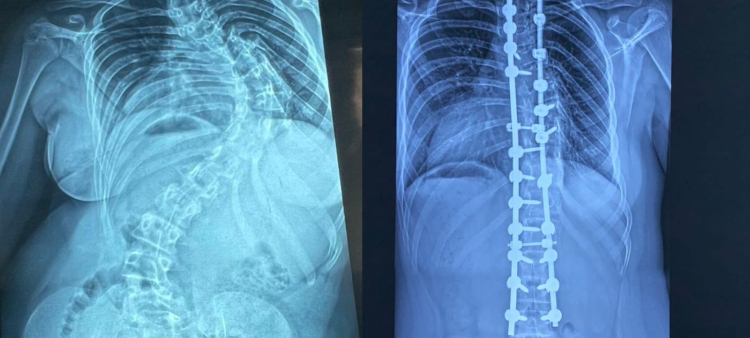

Bodies: Cuerpos Humanos Reales, abierta hasta el próximo 31 de octubre, exhibe ocho cuerpos humanos reales, cinco torsos y más de cien órganos y estructuras anatómicas.